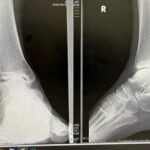

外反母趾:本当の原因を解き明かす

お題の外反母趾はこれまでも何度か投稿していますが、今回はちょっと難しいですがSTJ軸の視点で外反母趾の原因についてお伝えしたいと思います。最後までご視聴ください。

STJ軸インソール外反母趾姿勢足のアーチ踵運動連鎖